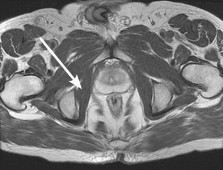

Question 6:

In designing a cementless femoral stem for a total hip arthroplasty, the manufacturer utilizes a porous coating. What pore size range is optimal for reliable biological bone ingrowth?

Correct Answer: 50-400 micrometers

Explanation:

The optimal pore size for biological bone ingrowth in cementless arthroplasty implants is generally between 50 and 400 micrometers. Pores smaller than 50 µm are too small for osteons and lead predominantly to fibrous tissue ingrowth, whereas pores larger than 400 µm decrease the structural integrity of the coating and increase the risk of micromotion.